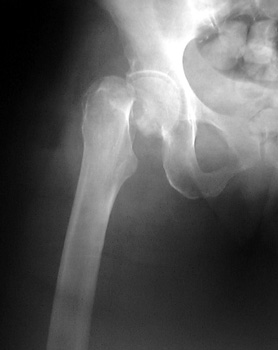

Bipolar hemiarthroplasty placed in patient with Garden IV hip fracture